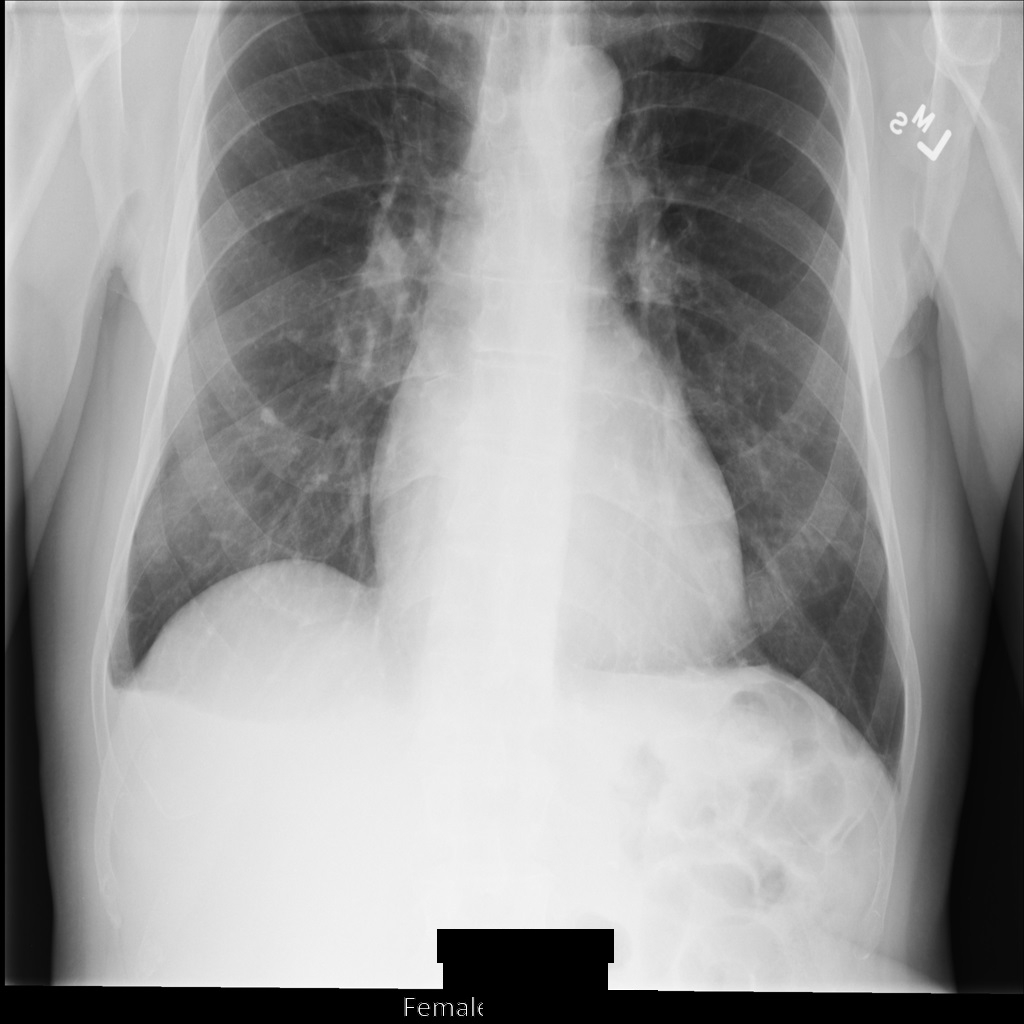

After de-identifying the image using REDACT_SENSITIVE_TEXT_CLEAN_DESCRIPTORS, the image looks like this. Notice that not all the burned-in text at the bottom of the image has been redacted. The text Female is still shown, because PatientSex (0010,0040) isn't one of the default DICOM infoTypes.

Figure 2. The DICOM instance after de-identification using REDACT_SENSITIVE_TEXT_CLEAN_DESCRIPTORS.